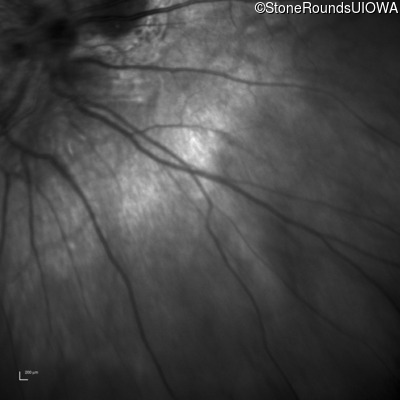

This 9 year old male was noted to have some crossing of his eyes at 2 months of age and the eye exam which followed identified a retinal lesion in the right eye. When he was six years old an epiretinal membrane was noted in his left eye. Two years later it was decided that it was a thin hamartoma in that eye as well. He underwent neuroimaging at age 7 which identified bilateral acoustic neuromas.